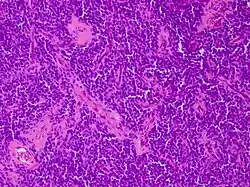

Micrograph of an H&E stained section of a peripheral PNET.

Primitive neuroectodermal tumor is a malignant (cancerous) neural crest tumor.[1] It is a rare tumor, usually occurring in children and young adults under 25 years of age. The overall 5 year survival rate is about 53%.[2]

It gets its name because the majority of the cells in the tumor are derived from neuroectoderm, but have not developed and differentiated in the way a normal neuron would, and so the cells appear "primitive". PNET belongs to the Ewing family of tumors.